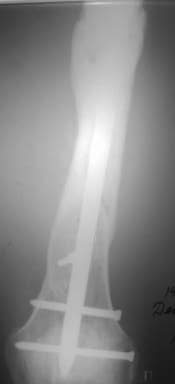

Отправитель: Сергей Зырянов 16 Декабрь 2005, 08:20

Александр Николаевич, к сожалению больной не является на контрольные осмотры. Я последний раз видел больного, когда прошло 7 месяцев после операции БОС. У него все хорошо. Каких либо жалоб и ограничений в нагрузке нет. Высылаю снимки до операции и последние снимки.